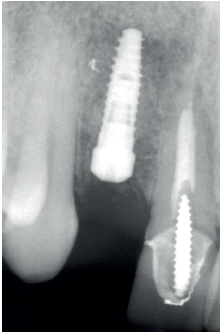

Para continuar con el estudio del caso se realiza un Cone-Beam donde poder observar tridimensional ente la posición del implante situado en posición 1.2. En los cortes seccionales se visualiza completamente situado hacia vestibular con una reabsorción casi completa de la cortical ósea de esta área, lo que explica los problemas de tejido blando subyacente. En la radiografía periapical se observa la posición del implante con respecto a los dientes adyacentes

(Figuras 5 y 6). Con esta imagen se procede a la apertura de un colgajo y la explantación del implante. Se retira también la corona situada en el diente 1.1 para poder realizar otra corona que servirá para apoyar el provisional en extensión para la zona del 1.2, mientras cicatriza la primera intervención. En este primer abordaje se coloca también un injerto en bloque obtenido de la rama mandibular que se fija con un microtornillo en la zona a regenerar donde se ha perdido la cortical vestibular. Una vez fijado y posicionado, se rellena alrededor del injerto en bloque con hueso particulado obtenido con un bone-scraper de la misma zona donante embebido en PRGF-Endoret para una mejor fijación y viabilidad celular (Figuras 7-9).